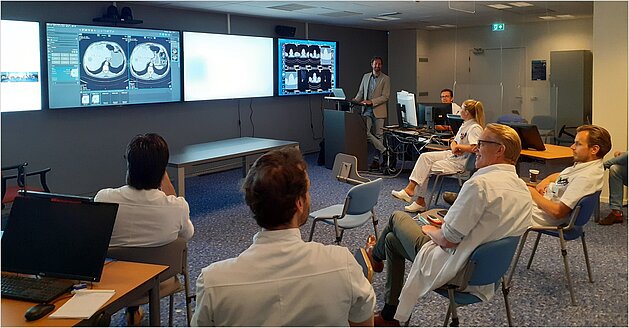

The desire to standardize reporting and to get even more out of their oncological images led to the partnership of the Noordwest Ziekenhuisgroep in…